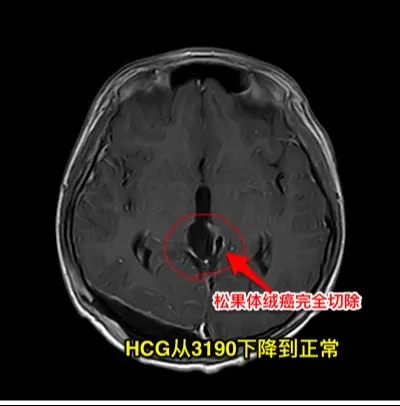

松果体区的绒毛膜癌(绒癌)很罕见。通常情况下,绝大多数的绒癌与女性怀孕过程的滋养细胞有关系,可以造成子宫内出血。 但是,脑部有一种恶性肿瘤称为绒癌,是生殖细胞肿瘤中的一种,很罕见,一般见于鞍区和松果体区。 这个11岁济宁市的男孩子于2024年10月底18日突发头痛、恶心、呕吐,在当地医院行头部CT检查发现了脑部有出血,出血的位置位于松果体区及第三脑室里,和普通的脑出血位置不一样。经过急诊手术(脑室外引流术)后保住了生命。磁共振检查显示松果体区有个肿瘤,考虑是肿瘤卒中出血了。转到我院化验HCG,达到正常值的600多倍。 2024年10月27日在我科作了手术,将肿瘤切除了,手术后小男孩身体恢复顺利,HCG逐步下降到正常范围。病理报告是纯绒癌! 这个脑部的绒癌是生殖细胞肿瘤中的一种,恶性度高,手术后需要作化疗+放疗。